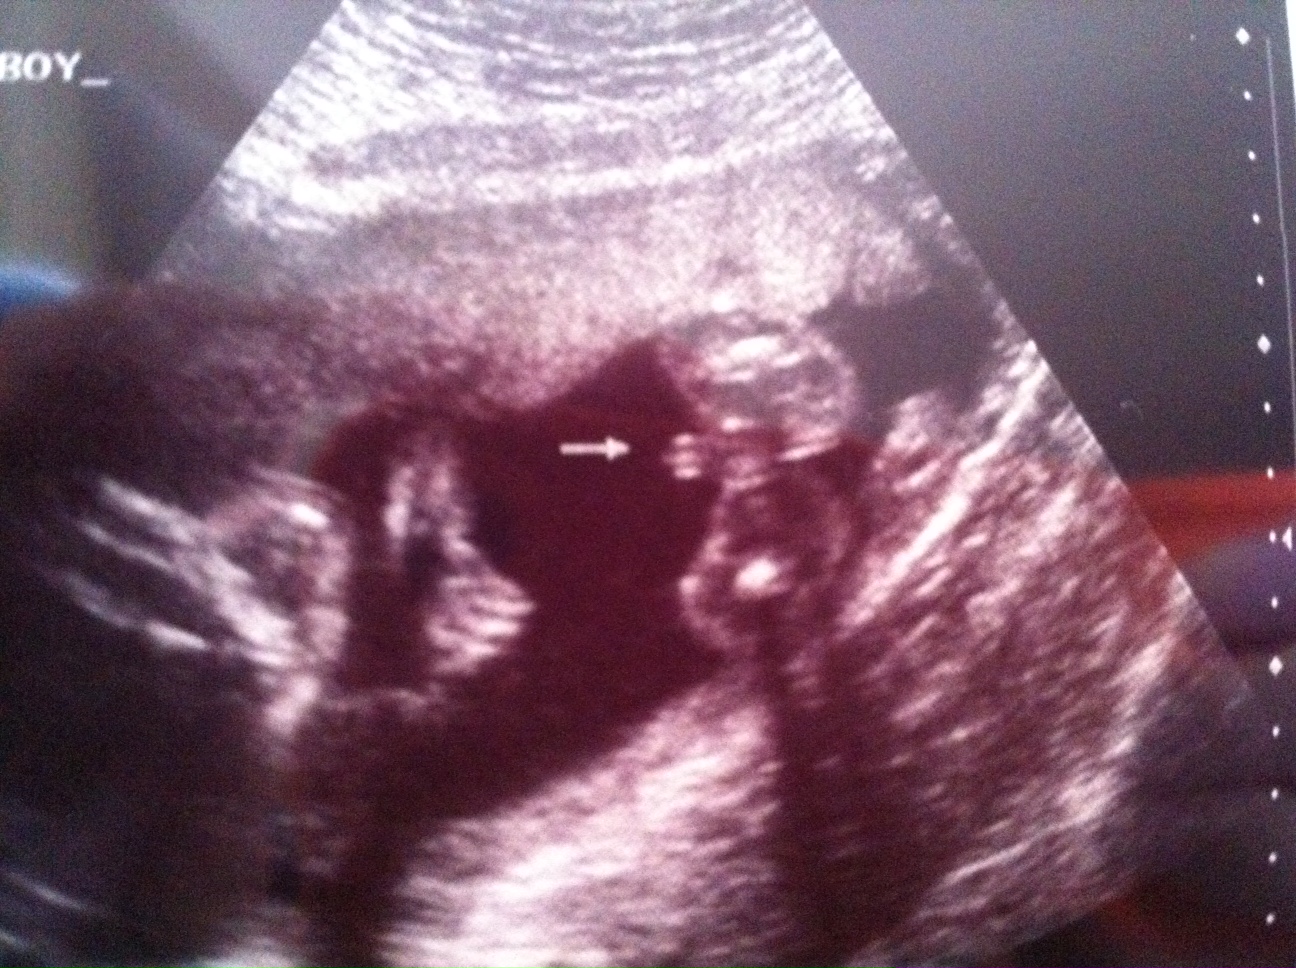

14 week u/s pointed to boy, 20 week u/s leaning towards girl. . . .need another opinion here. :-)

I had a funsies ultrasound in Illinois and was led to believe that my little one was a boy, which fell in line with my thoughts and feelings. However, I had the anatomy scan at 20 weeks and the tech said that she was "pretty sure" then "99.9" sure that it was a little girl.

Attachment 12403Attachment 12404Attachment 12403Attachment 12404